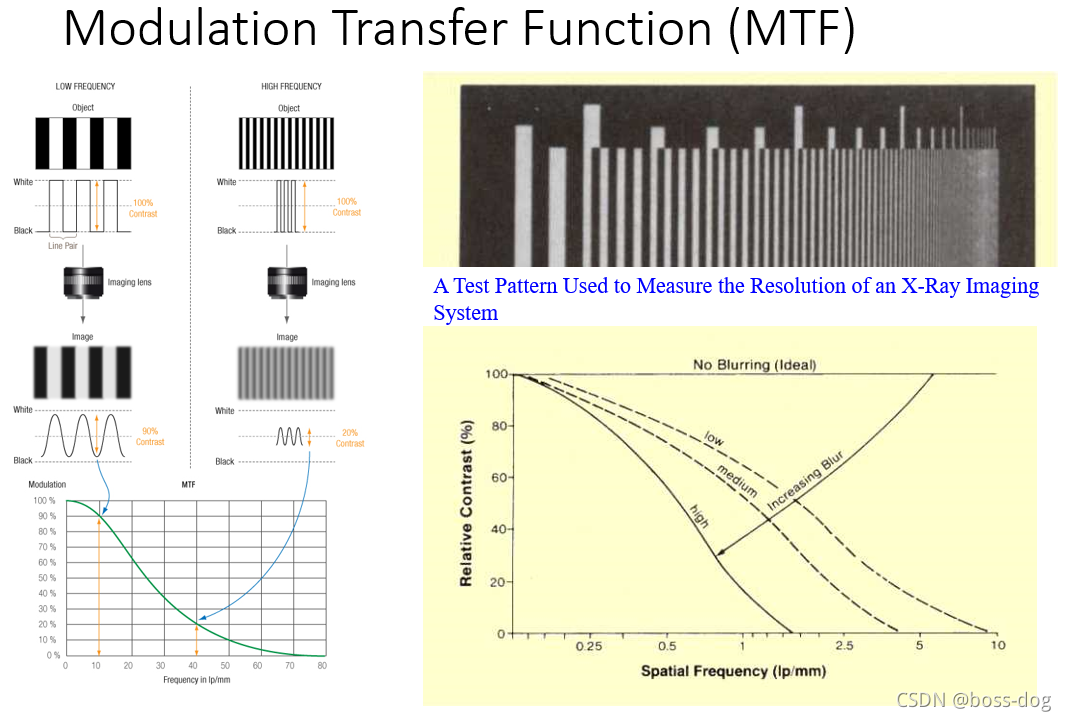

分辨率

复合成像系统的MTF

任何成像系统的MTF都是该系统各部件MTF的乘积。在每毫米5个周期的空间频率下,x射线胶片-屏幕成像系统各部件的MTF为焦斑0.9,运动0.8,和强化屏幕0.7。

则复合成像系统的MTF为0.9 × 0.8 × 0.7=0.5。